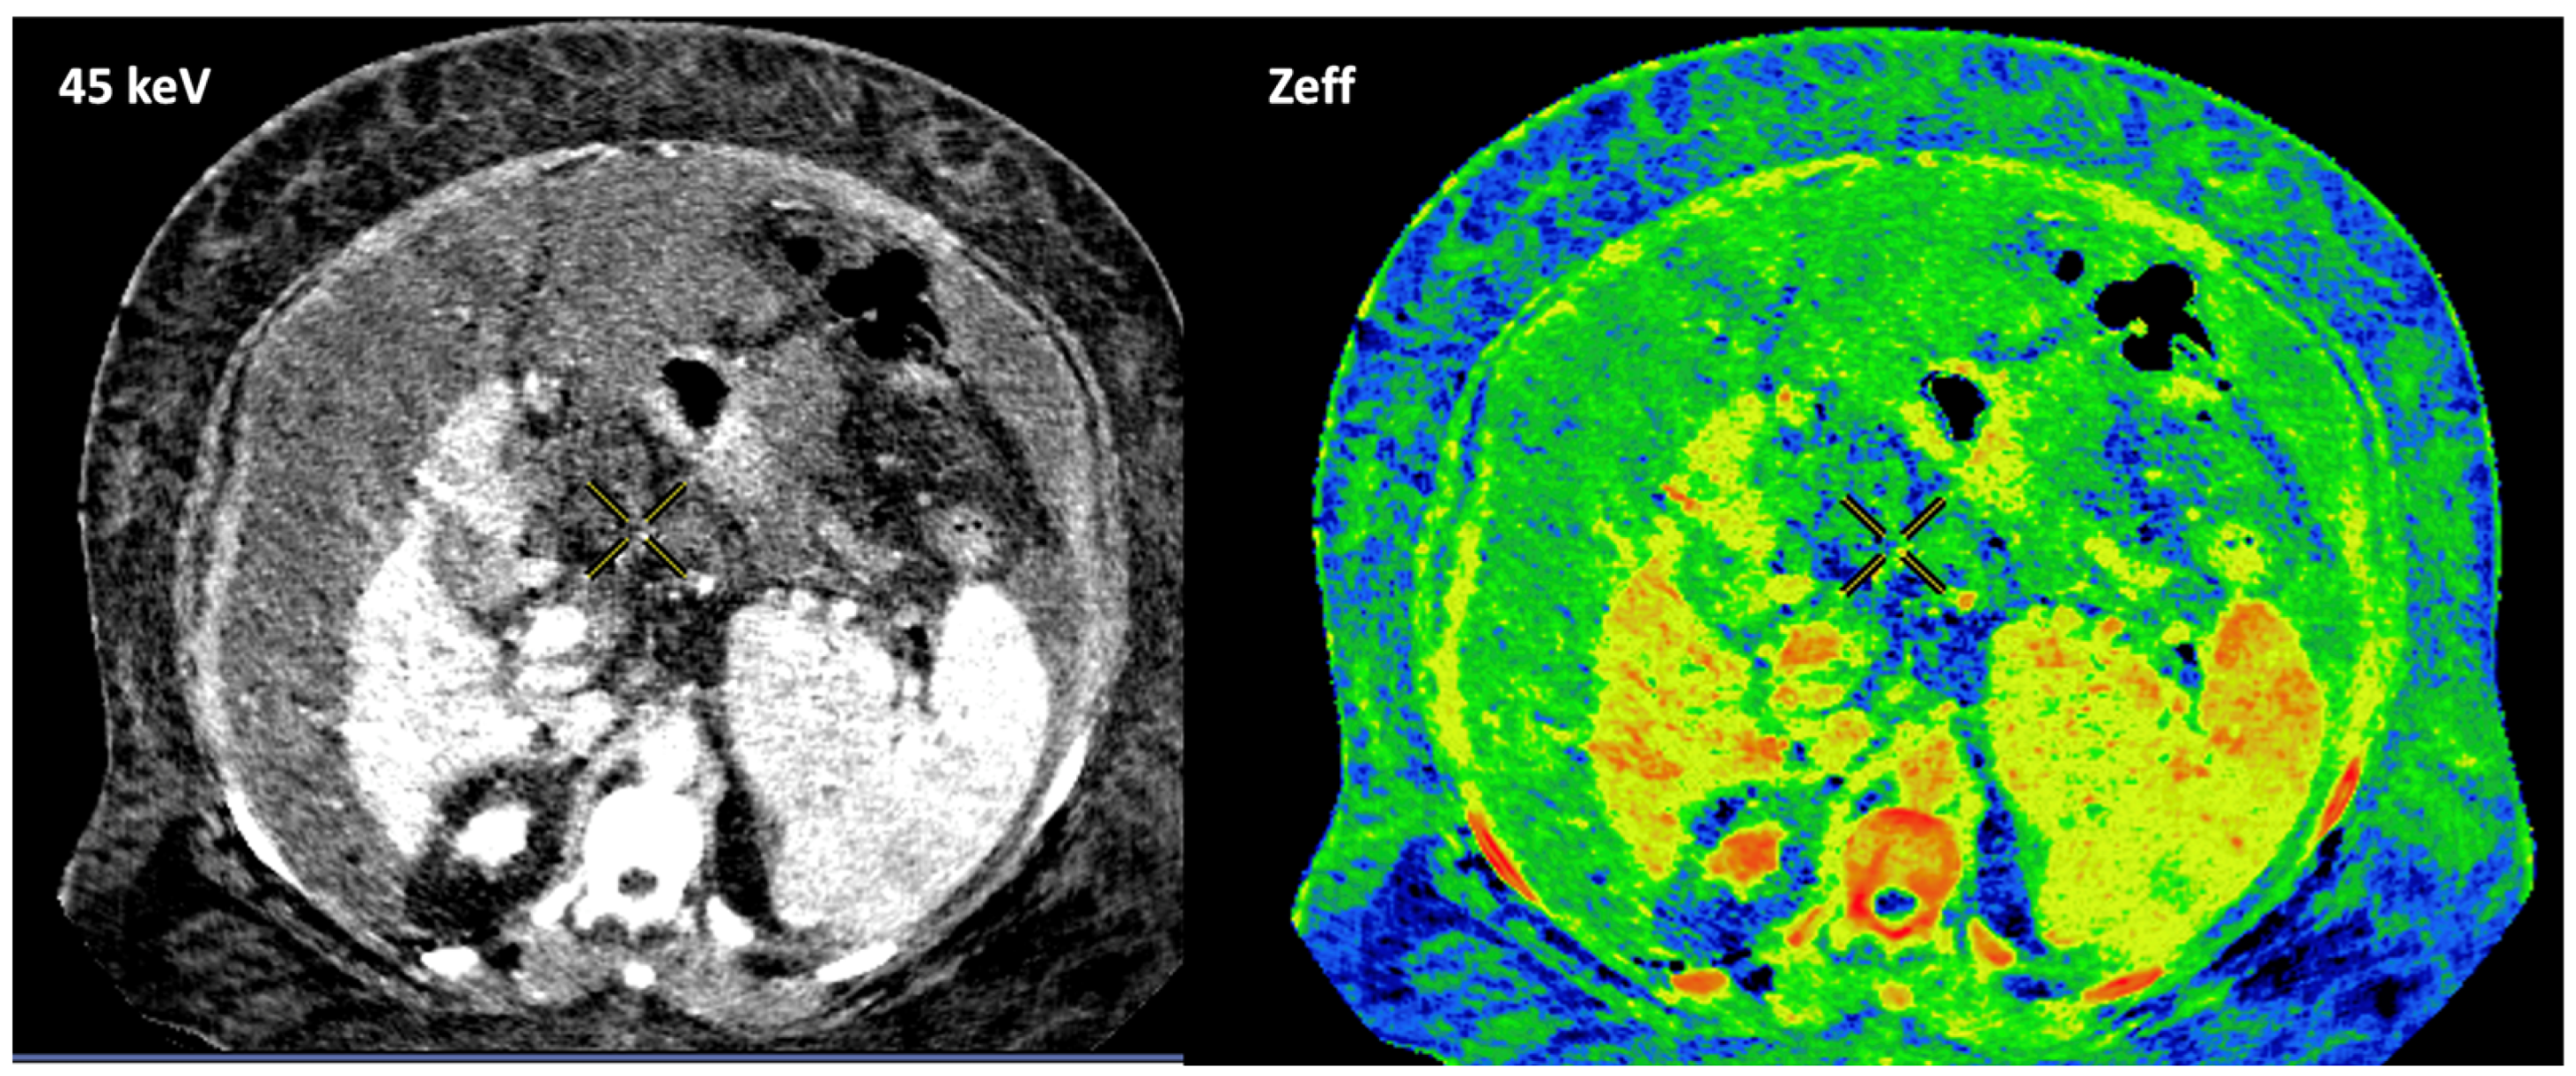

- Zeff is also a quantitative index for characterization of the composition of a voxel, although determining a biological correlation of these changes to tumor microenvironment is challenging.